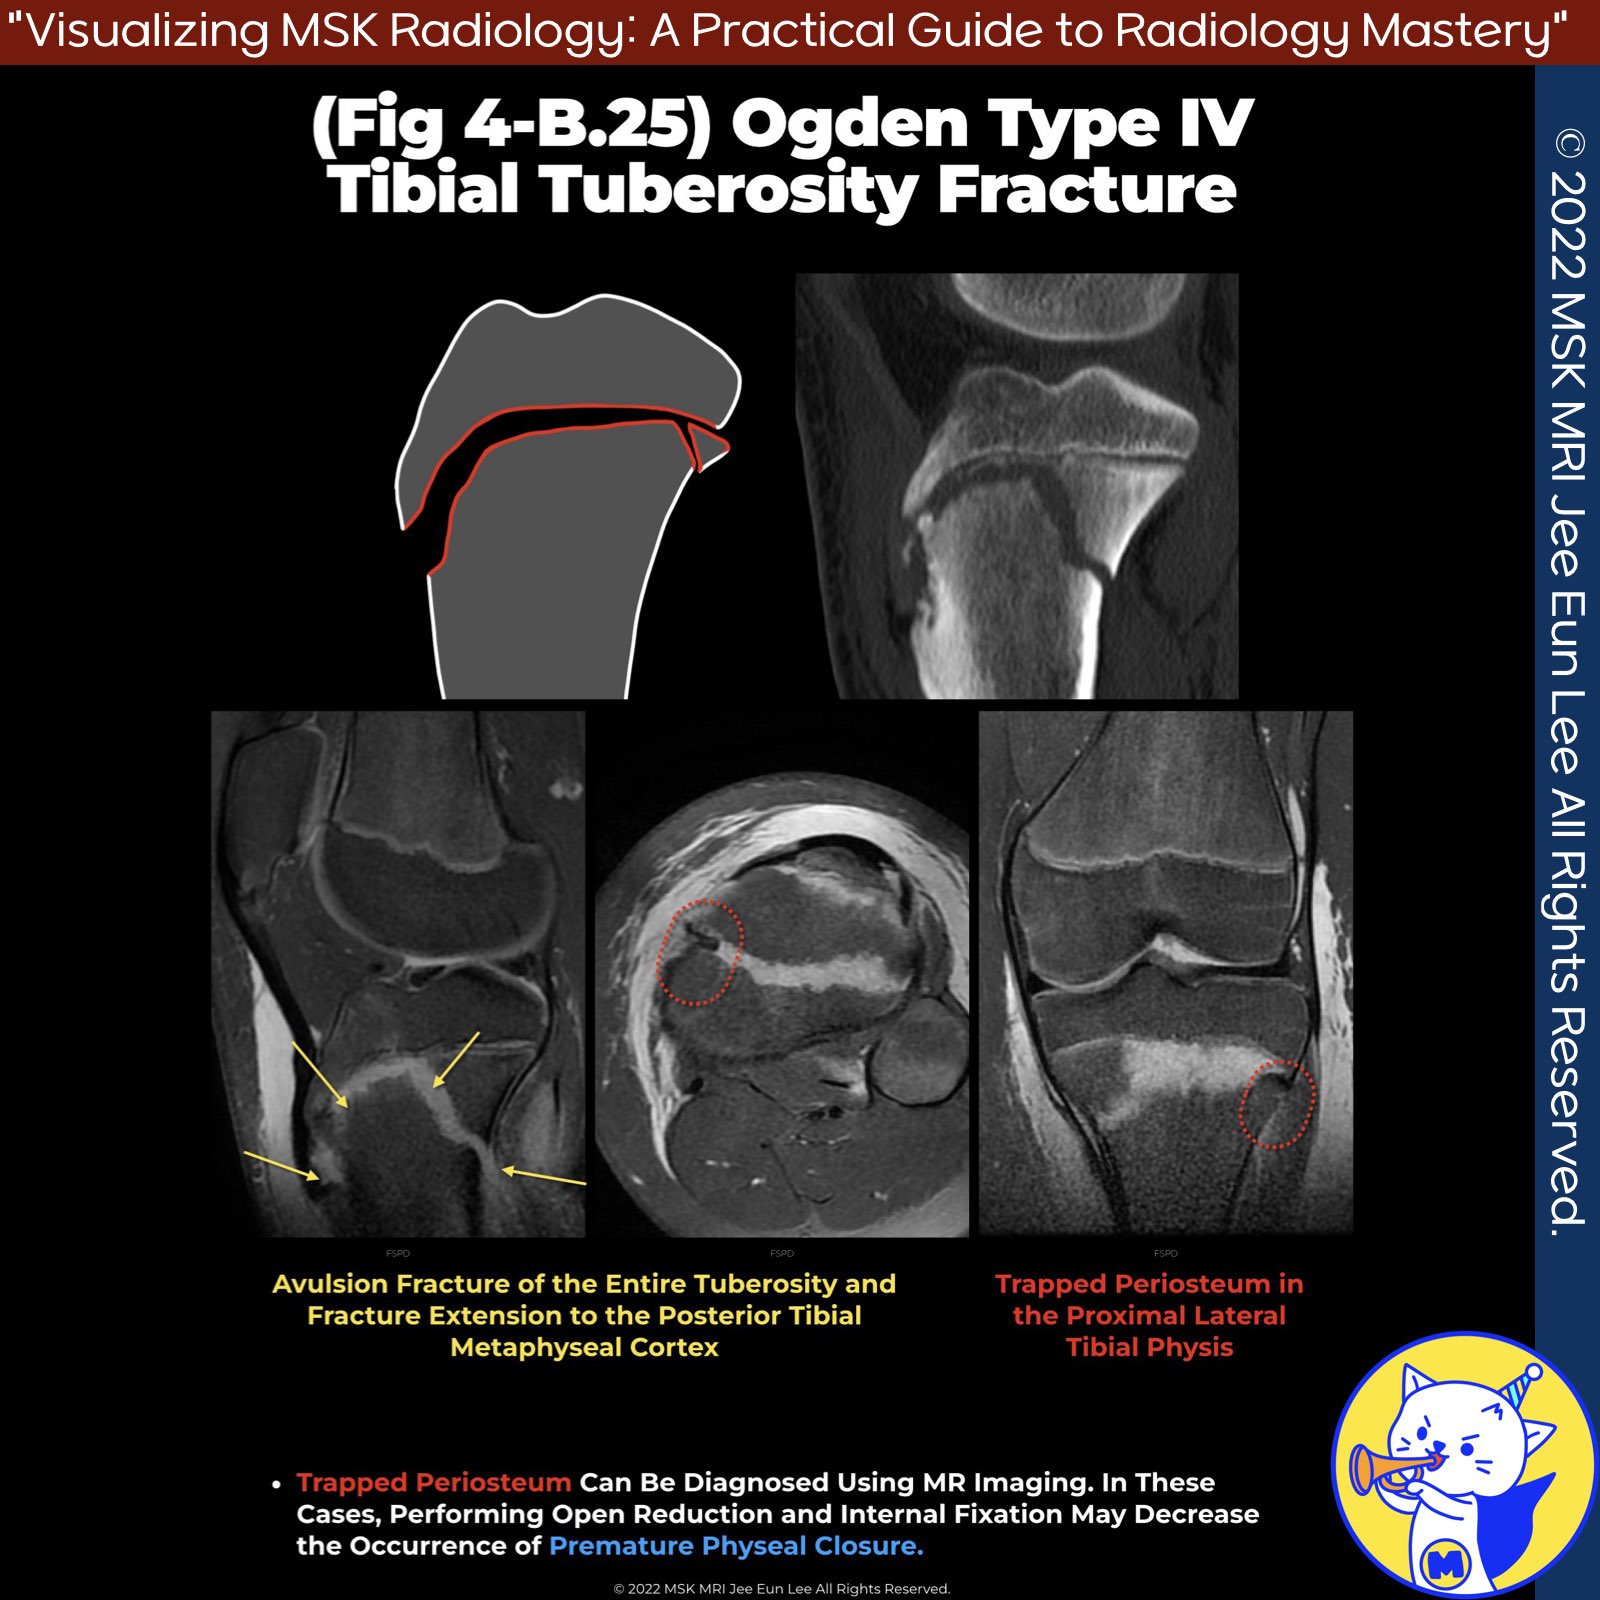

📌 Trapped Periosteum in Pediatric Proximal Tibial Physeal Injuries

- MRI guides surgical planning when conventional reduction fails, potentially improving outcomes.

✅ MRI Findings of Trapped Periosteum:

- widening of proximal tibial physis

- Enfolded periosteum in widened tibial physis

- Low signal intensity of trapped periosteum in growth plate

✅ Type IV Fractures

- Type IV fractures present with fracture extension from the tibial tuberosity through the proximal tibial physis into the posterior tibial metaphyseal cortex.